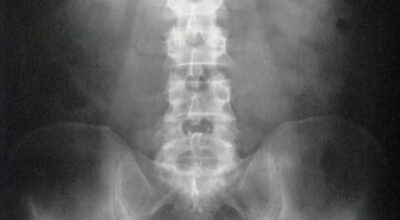

Esta recopilación de imágenes recoge alguna de las situaciones más estrambóticas que se han podido dar en una sala de rayos X. Todas ellas tienen algo en común: Son objetos extraños para el cuerpo humano que, de alguna manera han encontrado una vía de entrada, pero se han perdido a la hora de encontrar la de salida.

Muñecas de juguete descabezadas, botellas, armas, frascos, botes de plástico, teléfonos y hasta una cinta de casete pueden encontrarse en esa suerte de “punto limpio” al que ha quedado reducido el interior de los afectados.